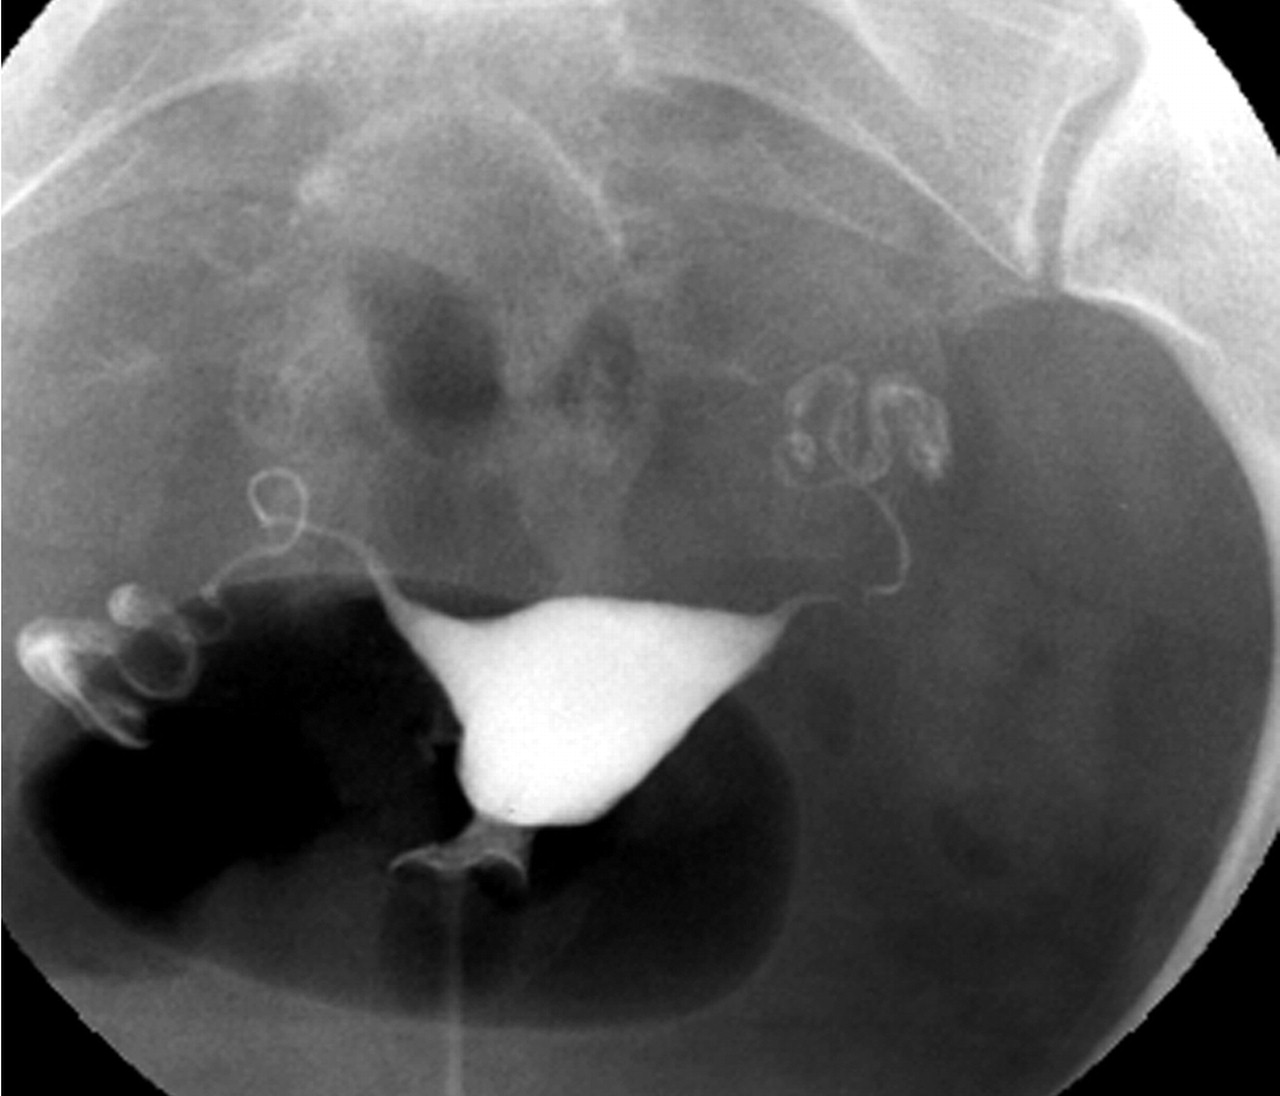

자궁경관에서 자궁강내에 조영제(造影劑)를 주입하고 자궁경관과 자궁강의 크기와 형상, 난관의 소통성, 골반복막의 상황, 유착의 유무, 난소종양의 유무 등을 X-선상(線像)으로 진단하는 방법이다.

⇒ 보통 자궁난관조영술은 자궁 및 난관(나팔관)에 조영제를 사용해서 자궁안쪽에 혹은 없는지 그리고 자궁의 크기나 모양은 괜찮은지 마지막으로 나팔관이 막혀있지는 않은지 등을 조영제를 사용해서 확인하는 방법이다.

사진을 보시면 자궁경부 입구  주사기 안에 들어 있는 조영제를 순차적으로 점점 밀어 넣게 됩니다.

그래서 만일 나팔관이 막혀 있지 않다면 자궁안을 채우고 난 이후 나팔관으로 순차적으로 조영제가 빠져 나가는 것이 확인이 되겠지만, 만일 자궁에 혹이 있는 경우엔 그 부분이 검게 뚫어져 있을 것이고, 나팔관이 막혀 있다면 나팔관 바깥쪽으로 조영제가 빠져 나가질 않을 것입니다.